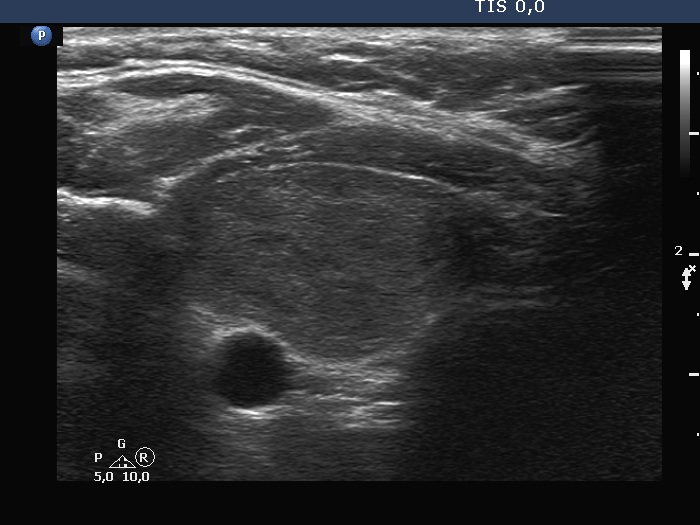

Ultrasonography. The thyroid was echonormal. There was a moderately hypoechoic nodule in the right lobe. The lesion presented halo and both perinodular and intranodular blood flow. The dimensions were 18x11x20 mm, width, depth, length, respectively. The left lobe had a cystic nodule which presented back wall cystic figures but not microcalcifications. The dimensions were 18x16x27 mm, width, depth, length, respectively.